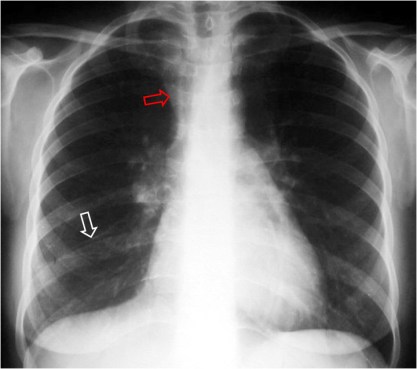

SIGNO DEL TRIÁNGULO SUPERIOR

Signo de colapso del lóbulo medio derecho o del lóbulo inferior derecho que consiste en la presencia de una densidad triangular en la zona paramediastínica derecha (flecha roja) que corresponde a la zona de convergencia de las líneas pleuromediastínicas anteriores, desplazadas a la derecha por el colapso. El descenso de la posición de la cisura menor (flecha blanca) confirma la pérdida de volumen en el lóbulo medio, en este caso.

Otro ejemplo de este signo, en este caso por pérdida de volumen en el lóbulo inferior derecho. No es visible la cisura menor, pero puede observarse el descenso del hilio derecho.